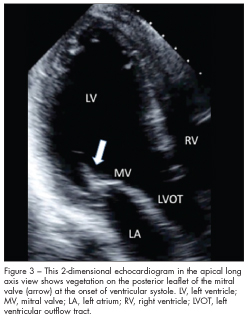

Echocardiographic images are obtained (Figures 1, 2, and 3). They demonstrate severe mitral regurgitation with a mobile, echogenic density on the posterior leaflet of the mitral valve (2.0 by 3 1.9 cm).